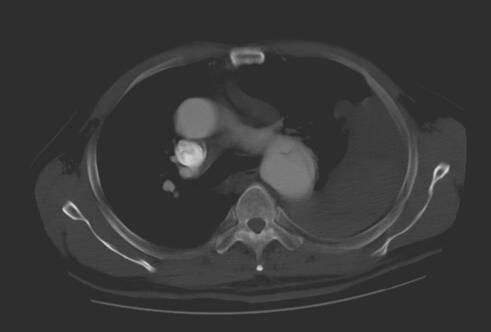

術前見主動脈夾層,胸腔大量積液和血凝塊

2014年3月18日20點55分,呼嘯而至的120救護車在郴州市第一人民醫(yī)院中心醫(yī)院急診室嘎然停下。初步檢診后明確患者既往有高血壓病史8年余,10余天突發(fā)劇烈胸背部疼痛,1小時前因突然暈厥而被120急診送入院。醫(yī)院綠色通道迅速啟動,相關科室10多位已經下班回家的醫(yī)護人員被緊急召回,時間就是生命,一場生死營救迅速展開。老人直接從急診室轉送至ICU病房,予快速補液、抗休克等對癥支持治療,病人生命體征逐漸趨于平穩(wěn),緊急完成主動脈CTA后,診斷患者胸主動脈夾層,胸腔大量積液及血凝塊。 血管外科病區(qū)主任鄭翼德副主任醫(yī)師在仔細查看病人后考慮患者有主動脈夾層破裂可能。 ?